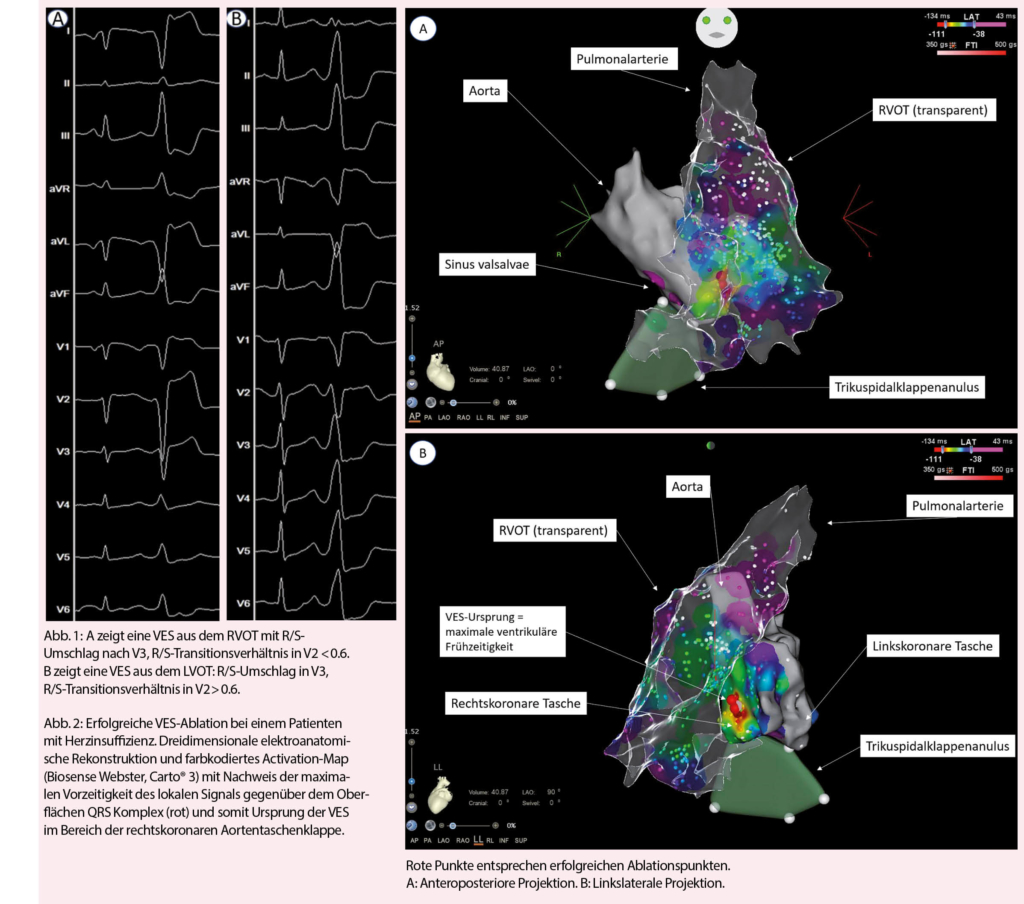

VES sind eine sehr häufige Rhythmusstörung mit einer geschätzten Inzidenz von 75% in der Gesamtbevölkerung und 95% bei Patienten mit Herzinsuffizienz (1-3). Die Prävalenz und Häufigkeit steigen mit dem Alter, kardiovaskulärem Risikoprofil und den assoziierten Komorbiditäten (4-6). Bei Erstdiagnose sollten strukturelle Herzerkrankungen ausgeschlossen werden, da sich VES bei diesen Patienten wesentlich von den idiopathischen VES ohne zugrundeliegende Herzerkrankung unterscheiden. Bei Ersteren treten VES oft im Zusammenhang mit einem Substrat auf und sie sind häufiger im linken Ventrikel lokalisiert mit resultierender Rechtsschenkelblock-Morphologie (7). Ist der Ursprungsort der Ausflusstrakt, dann ist es häufiger der linksventrikuläre oder auch anatomisch benachbarte Strukturen (8). Im Gegensatz dazu treten die idiopathischen VES ohne strukturelle Herzerkrankung durch die Mechanismen der getriggerten Aktivität oder Automatizität auf, insbesondere bei Frauen im jungen Erwachsenenalter. Bei diesen Patienten entstammen die VES in circa 70-80% aus dem Ausflusstrakt (9, 10) und dabei typischerweise aus dem unmittelbar subvalvulären Myokard des rechtsventrikulären Ausflusstraktes (RVOT) oder der myokardialen Extensionen bis knapp oberhalb der Taschenklappen der Pulmonalklappe (11). Klassischerweise zeigen RVOT-VES eine inferiore Achse mit Linksschenkelblock-Morphologie, aufgrund der Proximität anderer Strukturen können VES mit Ursprung im linksventrikulären Ausflusstrakt aber eine ähnliche Morphologie aufweisen (12). Hinweise für eine RVOT-Ätiologie im Oberflächen-EKG ist ein präkordialer R/S-Umschlag nach V3 oder später als im Sinusrhythmus, sowie eine QS-Morphologie in V1. Leider findet sich der R/S-Umschlag oft in V3 (Abb. 1) oder zeitgleich mit dem Sinusrhythmus (13), sodass der Ursprung letztlich nur während einer elektrophysiologischen Untersuchung genau lokalisiert werden kann. Bei einem R/S-Umschlag vor V3 kann jedoch nicht-invasiv das R-Zacken-Transitionsverhältnis in V2 (RVOT ≤ 0.6) zur weiteren Unterscheidung zwischen rechts- und linksventrikulärem Ursprung verwendet werden (14); dabei wird der Anteil der R-Zacke am gesamten vertikalen Vektor des QRS-Komplexes verglichen zwischen VES- und Sinus-QRS-Komplex. Ebenfalls prädiktiv für eine linksventrikuläre Lokalisation einer Ausflusstrakt-VES sind Alter>50 Jahre, männliches Geschlecht, kardiovaskuläres Risikoprofil und systolische Herzinsuffizienz (HFrEF) als Marker für eine strukturelle Herzerkrankung (15). Mittels Holter-EKG können VES durch Angabe des «Burden» (Prozentanzahl VES aller QRS-Komplexe) quantifiziert werden, allerdings kann damit die tatsächliche VES-Last aufgrund zeitlicher Variabilität der VES unterschätzt werden (16).

Eine Therapie-Indikation von VES besteht bei hoher Symptomlast, systolischer Herzinsuffizienz ohne eindeutig therapierbare andere Ursache, anhaltenden ventrikulären Tachykardien oder insuffizienter biventrikulärer Stimulation einer kardialen Resynchronisationstherapie. Bei asymptomatischen Patienten mit normaler LVEF und hohem VES-Burden empfiehlt sich ein expektatives Verhalten mit regelmässigen echokardiographischen Verlaufskontrollen, um die Entwicklung einer VES-assoziierten Kardiomyopathie rechtzeitig zu erkennen (41) – allerdings scheint das Intervall bis zur Abnahme der LVEF bei asymptomatischen Patienten mit gehäuften VES teilweise mehrere Jahre zu dauern und insgesamt einen sehr kleinen Anteil (geschätzte Inzidenz 5-7%) dieser Gesamtpopulation zu betreffen (36, 42). Lebensstil-Modifikationen im Sinne von reduziertem Alkohol-, Koffein- und Nikotinkonsum haben nur einen geringen Effekt auf die VES-Häufigkeit (43, 44). Ungefähr 25% der Patienten mit VES scheinen aber auf eine Kalium- oder Magnesiumsubstitution anzusprechen, wobei keine Daten bezüglich dem Effekt bei Herzinsuffizienz verfügbar sind (45). Betablocker können den VES-Burden gegenüber Plazebo signifikant senken (46), gleiches gilt für Amiodaron und Mexiletin, welche aber aufgrund des Nebenwirkungspotentials zurückhaltend eingesetzt werden (47). Klasse I Antiarrhythmika sind bei Patienten mit struktureller Herzerkrankung seit dem Nachweis einer erhöhten Mortalität von Flecainid in der CAST-Studie formal kontraindiziert, wobei das Resultat vermutlich primär durch eine heute obsolete Indikationsstellung (6VES/h = 144VES/24h) bei Patienten nach Myokardinfarkt zustande kam (48). Die elektrophysiologische Untersuchung mit RFA stellt eine interventionelle Alternative dar und muss bezüglich Eingriffsrisiko, Erfolgsaussicht und Eingriffsnutzen abgewogen werden. Die letzten zwei Jahrzehnte zeichneten sich durch enorme technische Fortschritte aus durch Entwicklung von dreidimensionalen Mapping-Verfahren mit Integration von Activation- und Pace-Mapping (Abb. 2, 3) und neue Erkenntnisse über den Effekt der RFA auf die langfristige Symptomlast, Morbidität und Mortalität. Entsprechend ist die Radiofrequenztherapie gemäss den aktuellen Leitlinien der europäischen Gesellschaft für Kardiologie eine Klasse I Indikation für die Behandlung von VES aus dem RVOT (49). Ernsthafte Komplikationen sind mit < 1% selten (39, 50). Gegenüber der pharmakologischen Therapie ist eine Ablationstherapie deutlich effizienter und anhaltender (Abb. 3) (51, 52). Der Erfolg einer RFA reicht von > 90% bei monomorphem Auftreten und Lokalisation im RVOT bis circa 60% bei Polymorphie, epikardialer oder Papillarmuskel-Lokalisation (39). Grundsätzlich ist eine RFA im Ausflusstrakt gegenüber anderen Lokalisationen mit einer grösseren Erfolgsaussicht verbunden, und ein Ursprung aus dem RVOT mit der besten Erfolgsaussicht überhaupt (Abb. 4) (53).